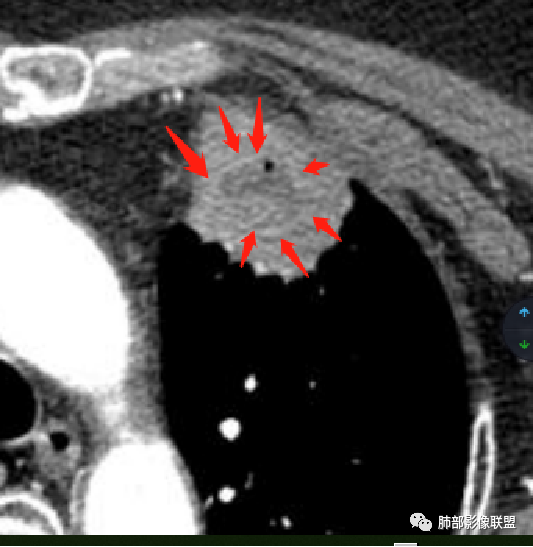

1、坏死区环形强化,指向慢性脓肿。

2、坏死区有血管,基本排除结核。

3、这个卫星灶,更进一步定了大方向,炎性。

※综上所述,看到这四幅图,基本能够准确诊断炎性※

3.病灶密度不均,中央坏死液化并见气泡影,支气管及血管贴边进入,较均匀环形强化(显示多层结构),未见明确壁结节。

3.病灶易坏死液化,环形强化,支气管及血管贴边进入,“火焰”样边缘轮廓,更符合炎性块影的特点。